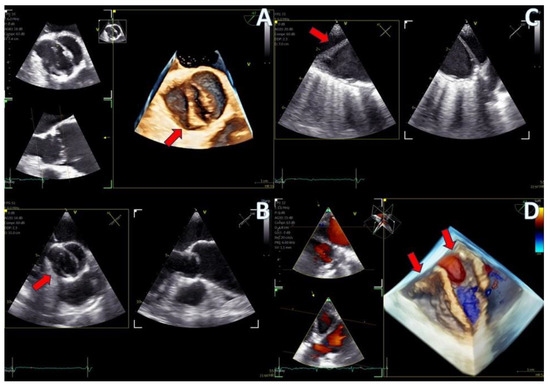

The adult probe was initially inserted for complete 2D/4D image acquisition, followed by the insertion of the pediatric probe while the patient remained under sedation. Remarkably, insertion of the pediatric probe was effortless in all cases, requiring no additional sedation. Despite encountering challenging diagnostic scenarios in all three cases (1st patient: combined severe aortic stenosis and severe mitral regurgitation (MR) due to P1 scallop prolapse, 2nd patient: malfunction of metallic mitral valve prosthesis with an occluded disk, 3rd patient: bioprosthetic aortic valve with paravalvular leak and significant MR in previously MV repair with a complete ring), the pediatric probe consistently provided high-quality images comparable to those obtained with the standard adult probe (Figure 1 and Figure 2, video S4). Notably, there was no compromise in 2D and 4D spatial and temporal resolution, with only minor differences observed compared to the adult 6VT-D probe (Table 1). Evaluation using the 5-point scoring system consistently yielded an average score close to 5 for all three cases, indicating excellent image quality (Table 1).

Figure 1.

Direct comparison of 3D volume −rendered “en face” images of a metallic prosthetic mitral valve with occluded disk. Left image corresponds to 6VT−D adult probe and right image corresponds to 9VT−D pediatric probe.